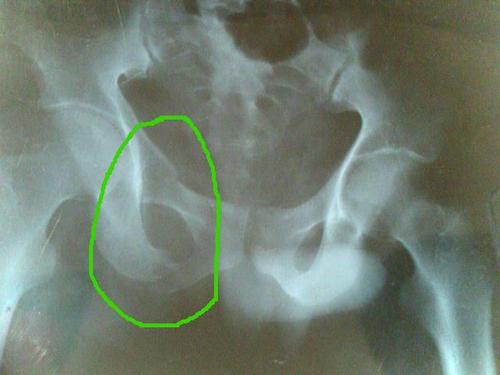

左侧坐骨支骨折图片

左侧坐骨支骨折图片,坐骨支骨图片

30 13:23:10坐骨支骨折 某男,48岁,因翻车砸伤骨盆,致左侧坐骨支骨折